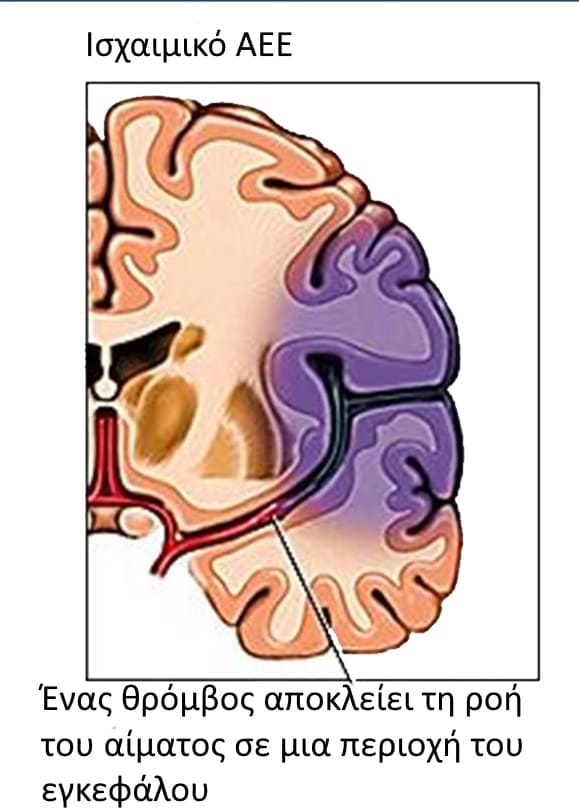

1. Ισχαιμικού Τύπου (Εγκεφαλικό ΄Εμφρακτο, «Stroke»)

Τα εγκεφαλικά επεισόδια ισχαιμικού τύπου οφείλονται στην έμφραξη ενός εγκεφαλικού αγγείου από θρόμβο ή έμβολο. Η ελάττωση της εγκεφαλικής αιμάτωσης στην περιοχή μπορεί να οδηγήσει σε λειτουργικές διαταραχές, οι οποίες είναι αναστρέψιμες εφόσον αποκατασταθεί έγκαιρα η αιμάτωση του εγκεφαλικού παρεγχύματος. Σε αντίθετη περίπτωση, επέρχεται ισχαιμική νέκρωση. Οι παθολογικές καταστάσεις που προδιαθέτουν για ισχαιμικά εγκεφαλικά επεισόδια στο σκύλο είναι:

Ένας θρόμβος αποκλείει τη ροή του αίματος σε μια περιοχή του εγκεφάλου.